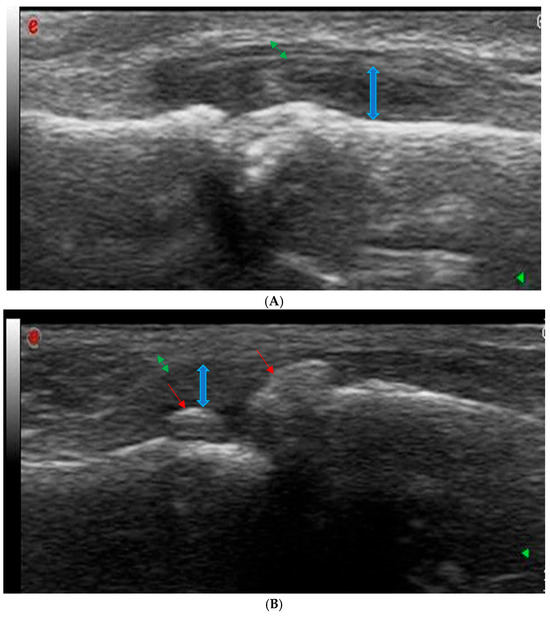

2.3. Ultrasonography Examination